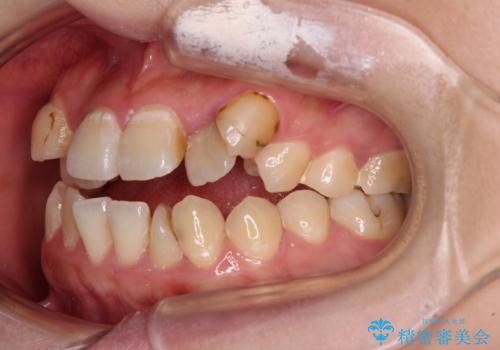

- 上下の歯が非接触であり、八重歯やむし歯を気にして来院された患者様です。

下顎骨の左右偏位はあるものの、上顎骨幅が相対的に狭い状態であったので、奥歯の咬み合わせが非常に乱れていました。

急速拡大装置により上顎骨幅を側方に拡大し、それを利用して八重歯を歯列に納めることにしました。

矯正治療後は全顎的にむし歯が多いため、セラミッククラウンやインレーにより補綴治療を行うこととしました。

急速拡大が奏効し、非抜歯矯正にて八重歯を解決することができました。